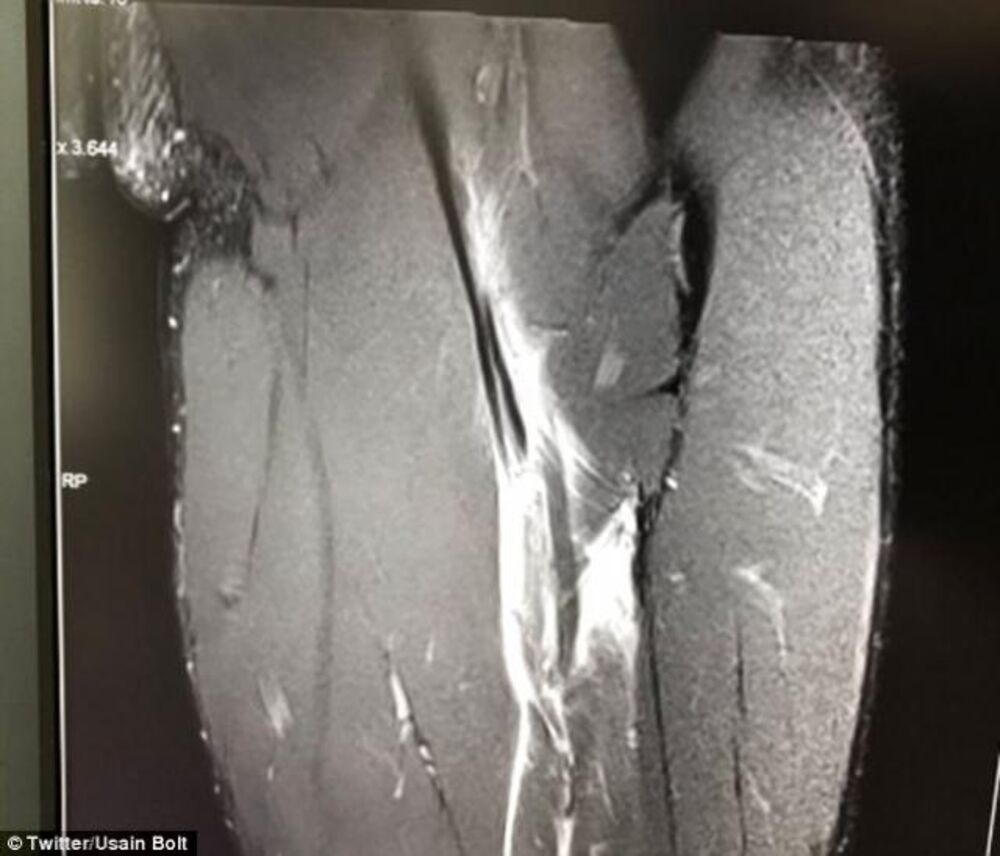

On je to oštro demantovao pokazavši na društvenim mrežama rendgenski snimak svoje povrede na kome se vidi da ima rupturu, ali je kasnije sporni tvit obrisao.

- Nažalost, imam pukotinu na mišiću i čeka me barem tri meseca oporavka. Inače nema običaj da objavljujem svoje medicinske nalaze u medijima, ali sam sada morao to da učinim jer sam bio tužan kada sam čuo priče i sumnje ljudi, koji su u pitanje dovodili moju povredu - rekao je Bolt i oštro demantovao priče o namernoj predaji.